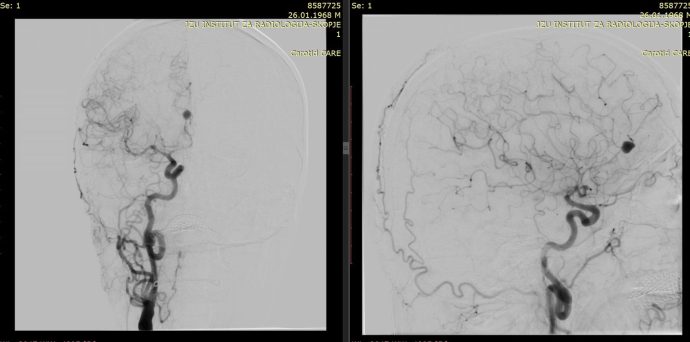

На Универзитетска клиника за неврохирургија беше извршена комплексна микрохируршка интервенција кај 57-годишен пациент со руптурирана аневризма на мозочен крвен сад.

Оваа иновативна метода претставува напредна техника која овозможува визуелизација на крвниот проток во реално време за време на операцијата.

– Со примена на контрастно средство, хирурзите можат прецизно да ја проценат проодноста на крвните садови и да го потврдат целосното исклучување на аневризмата, што е клучно за успешен исход, појаснува д-р Благој Шунтов, специјалист по неврохирургија и раководител на тимот.